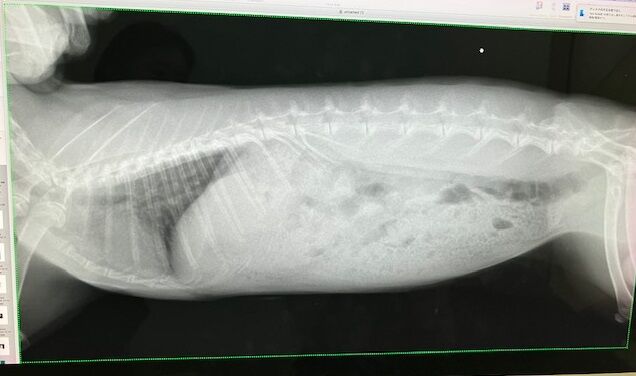

ビフォー

アフター

口はちゃんと届くことなく、傷跡もキレイ